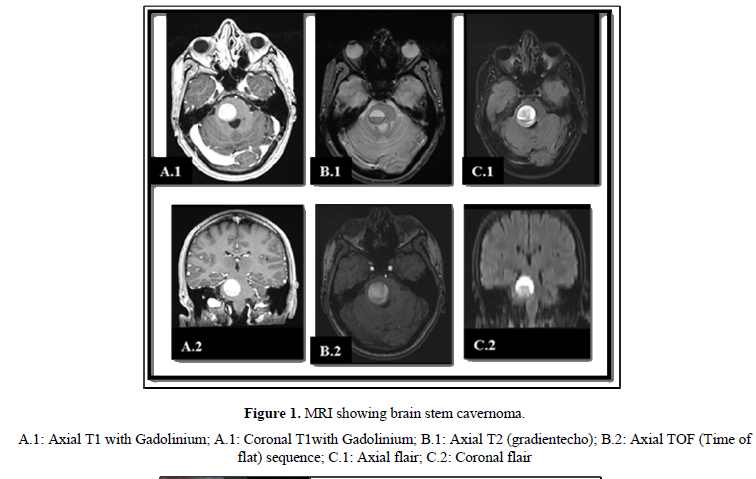

A 34 years old male patient with no medical background was complaining about limbs paresthesia followed in a week by left leg hypoesthesia and weakness leading to gait disturbance. The cerebral CT scan shows an acute pontine bleeding on the right side. The patient had been hospitalized for betamethasone corticosteroid therapy that decreased motors issues. After that he was released for a home follow up. Two months later he came for moderate headaches, swallowing issues, dizziness, diplopia and left sided weakness. The cerebral MRI demonstrated a pontine well definite lesion of about 29 x 26 mm (Figure 1), hyper intense on T1 weighted, hypo signal surrounding rim on T2 weighted and a blooming pattern on SW1. It also showed on diffusion sequences some surrounding artifact of blood degradation products. There was a slight mass effect on the fourth ventricle without any upstream hydrocephalus. These imaging characteristics strongly suggested a pontine cavernous malformation.